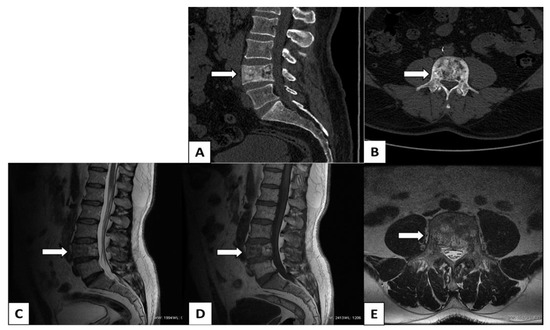

- Morales, H. MR Imaging Findings of Paget’s Disease of the Spine. Clin. Neuroradiol. 2015, 25, 225–232. [Google Scholar] [CrossRef]

- Feki, A.; Sellami, I.; Gassara, Z.; Ben Djemaa, S.; Ezzeddine, M.; Kallel, M.H.; Fourati, H.; Akrout, R.; Baklouti, S. Spinal Paget’s disease with bilevel cord compression and ischemic non-compressive myelopathy treated with zoledronic acid. Clin. Case Rep. 2022, 10, 6263. [Google Scholar] [CrossRef] [PubMed]

- Winn, N.; Lalam, R.; Cassar-Pullicino, V. Imaging of Paget’s disease of bone. Wien. Med. Wochenschr. 2017, 167, 9–17. [Google Scholar] [CrossRef]

- Whitten, C.R.; Saifuddin, A. MRI of Paget’s disease of bone. Clin. Radiol. 2003, 58, 763–769. [Google Scholar] [CrossRef] [PubMed]

- Lombardi, A.F.; Aihara, A.Y.; Fernandes, A.D.R.C.; Cardoso, F.N. Imaging of Paget’s Disease of Bone. Radiol. Clin. N. Am. 2022, 60, 561–573. [Google Scholar] [CrossRef]